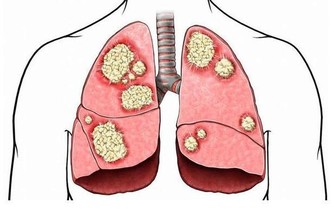

腹部、頸部青筋——肝病、心病 如果出現腹部青筋,說明是比較嚴重的積滯,往往是較難治的疾病,如肝硬化腹水、腫瘤後期等。脖子上持續有青筋凸起,說明兩種情況,一是心功能不全,多見於肺心病等疾病;二是心包炎或心包積液。 調理方法:如果這兩個部位出現青筋,則需要引起重視,及時就醫,切勿通過其他方法緩解症狀,以致延誤最佳的治療時機。